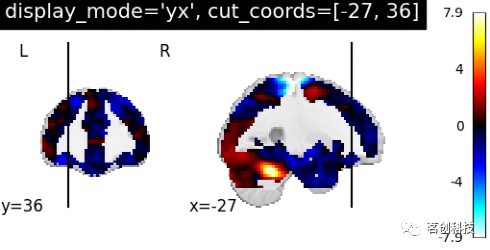

设置display_mode= 'yx',cut_coords=[-27, 36],表示在y和x方向上切割,手动定位。

plotting.plot_stat_map(stat_img, display_mode='yx',

cut_coords=[-27, 36],

title="display_mode='yx', cut_coords=[-27, 36]")